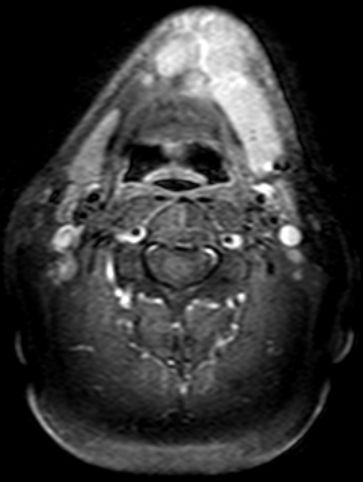

| MRT | 54-jähriger alkoholkranker Schlosser mit einem Tumor von Zungenrand, Zungengrund und Mundboden. | ||